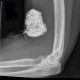

Ada pasien nih dok dengan keluhan siku tangannya bengkak dan nyeri. Setelah dilakukan rontgen ditemukan gambar berikut. Menurut dokter, apa penyebab lesi di dekat siku ini?

Penyebab adanya lesi pada tangan adalah ekstravasasi media kontras. Jika dokter memperhatikan dengan teliti akan tampak kanula IV yang masih terpasang di siku. Pasien akan mengeluh nyeri, bengkak, kemerahan dan gatal pada area tersebut.

Pada tata laksana inisial, dokter dapat memberikan kompres dingin dan elevasi lengan yang terkena. Tentukan volume kontras yang di injeksikan dan informasikan kepada dokter yang meminta pemeriksaan tersebut.

Lakukan observasi dan follow up hingga hari berikutnya (mungkin memerlukan beberapa kali follow up). Hal ini dilakukan untuk menilai: lepuhan kulit atau ulserasi, pembengkakan dan nyeri terutama yang berhubungan dengan perubahan perfusi atau sensasi.

Sebagian besar pasien tidak berkembang menjadi komplikasi tetapi volume yang besar ( > 50 mL) biasanya memiliki komplikasi. Komplikasi yang terjadi seperti ulserasi kulit, nekrosis jaringan lunak dan sindrom kompartemen.